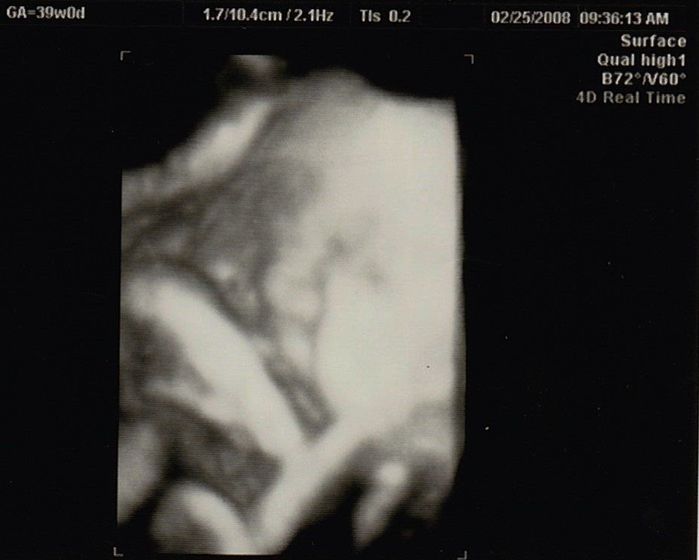

妊娠39週目のエコー写真

母や義母から「まだ生まれないの?」という電話と、たまたま出産予定日が日曜日で、夫、実父、義父も仕事が休み。その日に産まなきゃという義務感が生まれてきました。前日に自宅近くの坂道を上り下り、たっぷり散歩し、スクワットをした結果、無事、予定日当日に出産できました。

妊娠40週0日。予定日に7時間半の陣痛を経て生まれた赤ちゃんは、身長51cm、体重3568g。手足があるか、障害がないかなどが最初に頭に浮かび、元気な男の子が生まれたと分かった瞬間、「やっと終わったー!」いう嬉しさがこみ上げてきました。新生児室の中で一番ビッグで貫禄のある息子を見ると、自分の中からこんな赤ちゃんが出てきたのか、と変な感覚でしたが、毎日見ているうちにどんどん愛着が湧いてきました。赤ちゃんを産んだらというより、育てながらママになり、親子になっていくのだなと実感しました。私はたまたま何の問題もなく、出産まで順調でしたが、それでもとても大変でした。世の中のお母さんはすごい!